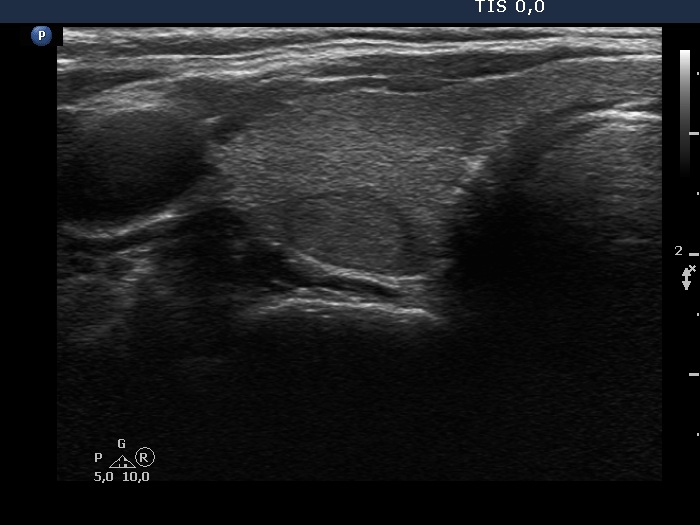

Thyroid cancers - case 727 (ultrasonographic picture 3)

Right lobe, another transverse scan. There is a nodule in the dorsal part which proved to be hyperplastic nodule on histopathology.